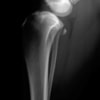

術前左後肢側面像

術前正面像

手術前後のTPA(脛骨高平部の角度)を測定しています。

約29°から約10°へ矯正されています。

本症例は、走った後に左後肢を挙上していることを主訴に来院されました。触診時に左膝関節のクリック音を聴取、レントゲン検査にて左脛骨の前方変位が認められました。術中に、前十字靱帯の断裂及び内側半月板の損傷、内側の軟部組織の顕著な腫脹を確認。半月板切除、TPLOを実施しました。周囲組織への炎症の波及もあったため回復に時間を要しておりますが、徐々に跛行頻度は減少傾向にあり、現在も経過観察中です。術前に約29°あったTPAは術後に約10°まで矯正されました。